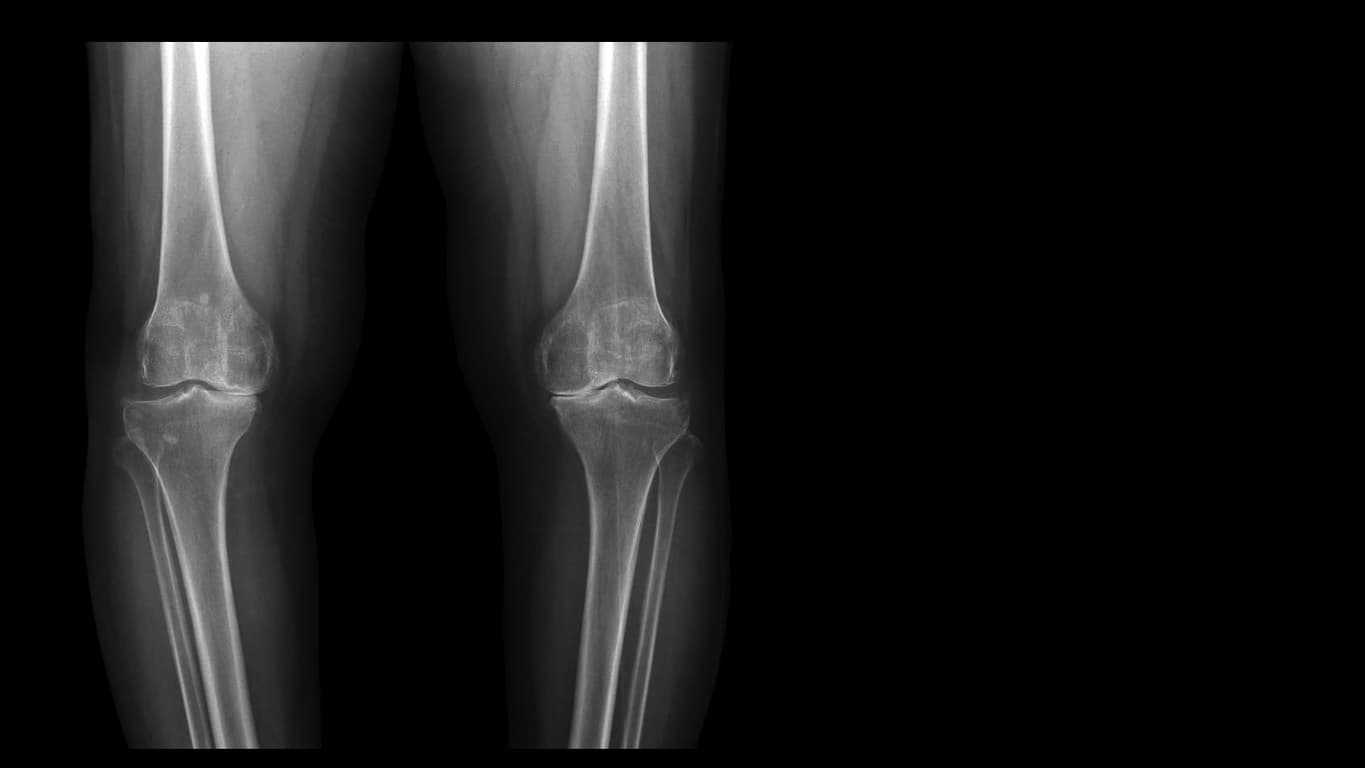

Die Forscher behandelten insgesamt 849 Patienten mit fortgeschrittener Arthrose von Knie- oder Hüftgelenk, die auf ihre bisherigen Medikamente nicht mehr ansprachen. In drei etwa gleich grossen Gruppen erhielten sie Placebo, Tanezumab 2,5 mg oder 5 mg, jeweils subkutan alle acht Wochen. Nach 24 Wochen sahen die Wissenschaftler, dass die 5-mg-Dosis von Tanezumab den kombinierten primären Endpunkt signifikant gebessert hatte. Er fasste Schmerzen im betroffenen Gelenk, die körperliche Funktionsfähigkeit und die Einschätzung des Patienten zu seinem Zustand (mittelmässig, schlecht, sehr schlecht) zusammen.